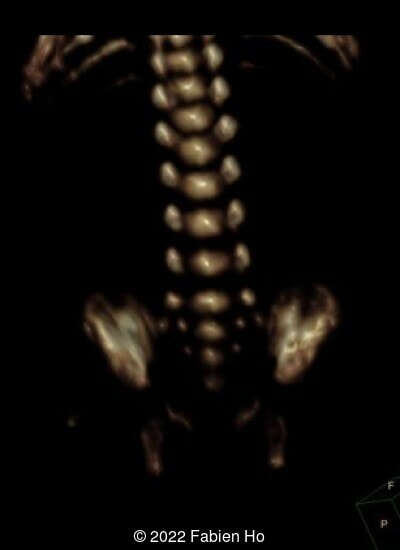

A CT scan was subsequently performed at 32 weeks gestation

The prenatal CT scan showed:

- Low bone density of skull and lower limbs

- Moderately narrowed and bell-shaped thorax

- Normal bone density of the spine

- No platyspondyly

- Normal pelvis without iliac spine or other anomaly

- Very short long bones with curved femurs, tibias and fibulas. The curvature of the long bones reaches a 90° angle concerning for fracture. Upper limbs are moderately curved without fracture.